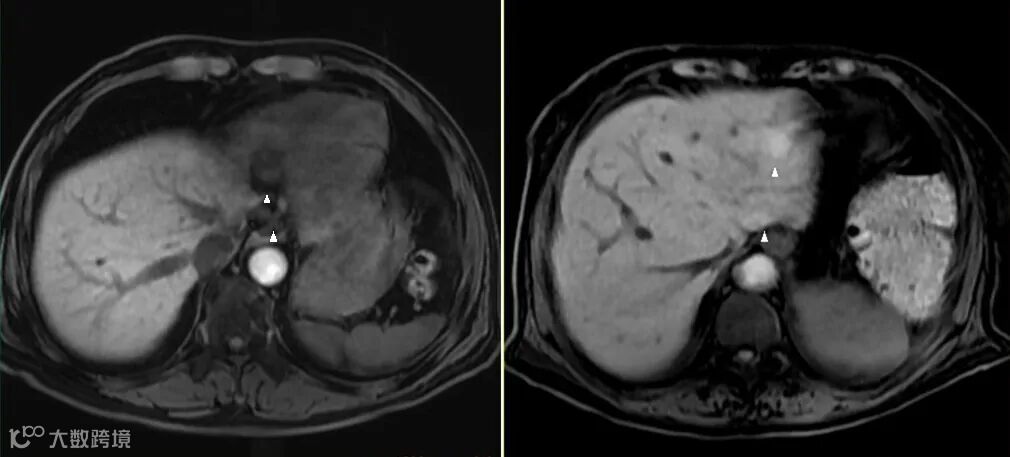

MRI上的信号是相对的,没有绝对的高与低,而要看与谁比,在解读MRI图像信号时要选取信号相对稳定的组织作为参照对比,如肌腱,脑脊液。 -

在增强机理方面,MRI“对比剂”与CT“造影剂”有着本质的区别。钆对比剂本身并不会产生信号,而是当钆对比剂与水分子的距离足够近时,通过缩短周围水质子的T1弛豫时间来间接产生“增强”的作用。切记不要以信号强度的高低来判定摄取对比剂浓度的多少。